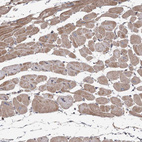

Immunohistochemical staining of human heart muscle shows moderate cytoplasmic positivity in cardiomyocytes.